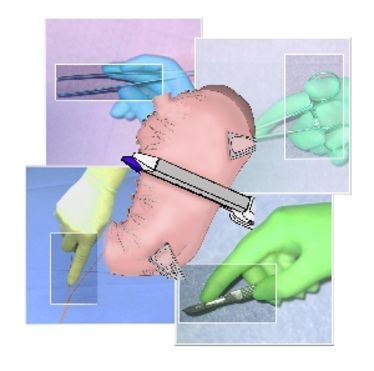

OP-Kurs "Mikrochirurgie der peripheren Nerven und Gefäße"

OP-Kurs "Mikrochirurgie der peripheren Nerven und Gefäße"